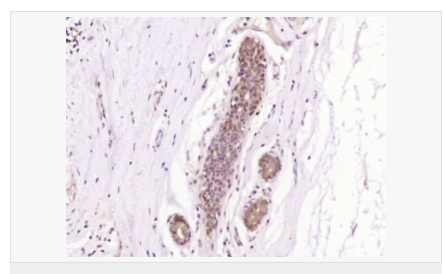

| 產(chǎn)品應用 | WB=1:500-2000 ELISA=1:5000-10000 IHC-P=1:100-500 IHC-F=1:100-500 ICC=1:100-500 IF=1:100-500 (石蠟切片需做抗原修復) not yet tested in other applications. optimal dilutions/concentrations should be determined by the end user. |

| 產(chǎn)品介紹 | Increase in fetal surfactant synthesis and lung maturity is caused by the glucocorticoidal induction of enzymes required for phosphatidylcholine synthesis towards the end of gestation (1). The regulation of gestational age-dependent induction of phosphatidylcholine synthesis by glucocorticoids is still unclear (1). The rate-controlling enzyme in the phosphatidylcholine biosynthetic pathway is CTP-phosphocholine cytidylyltransferase A (CCT A) (2–4). In cultured eukaryotic cells, this enzyme is essential for survival (3). The alpha isoform is located in the nucleus and is regulated by reversible phosphorylation and membrane association (3). There is significant identity between the alpha-helical membrane-binding domains of CCT A and soybean oleosin (2). Expressed CCT A has lipid-dependent cytidylyltransferase activity (5). The gene which encodes CCT A maps to human chromosome 3q (4). Function: Controls phosphatidylcholine synthesis. Subunit: Homodimer. Subcellular Location: Cytoplasm; cytosol. Membrane. It can interconvert between an inactive cytosolic form and an active membrane-bound form. Post-translational modifications: The serine residues of the C-terminus are phosphorylated. The inactive soluble form is stabilized by phosphorylation, the active membrane bound form is promoted by anionic lipids or diacylglycerol, and is stabilized by dephosphorylation. Similarity: Belongs to the cytidylyltransferase family. SWISS: P49585 Gene ID: 5130 Database links: Entrez Gene: 5130 Human Entrez Gene: 13026 Mouse Omim: 123695 Human SwissProt: P49585 Human SwissProt: P49586 Mouse Unigene: 135997 Human Unigene: 98775 Mouse Important Note: This product as supplied is intended for research use only, not for use in human, therapeutic or diagnostic applications. |